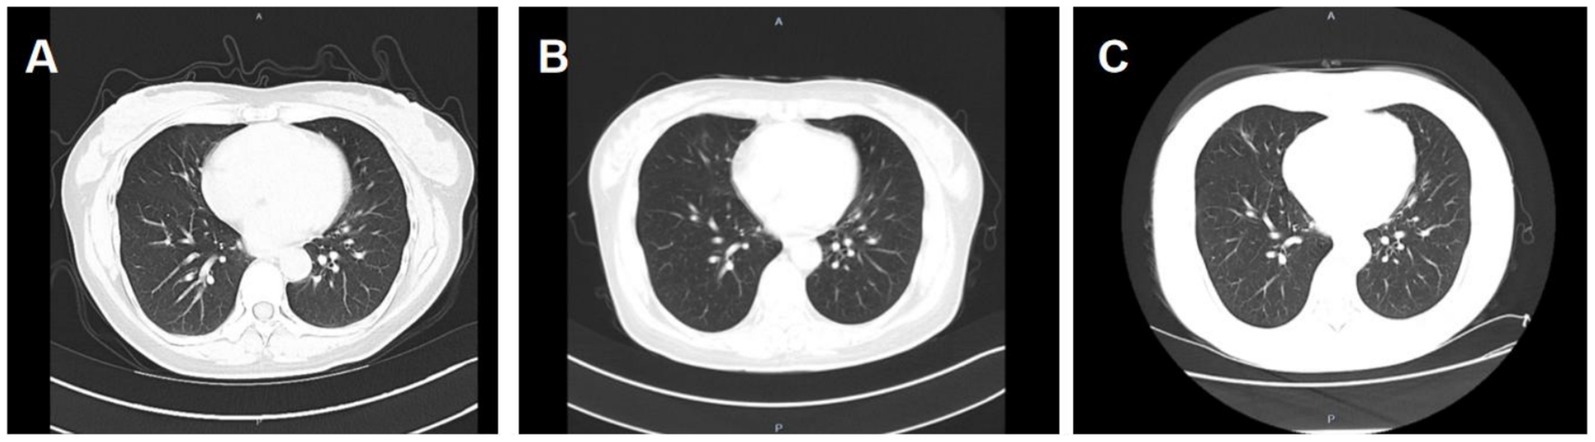

The patient was admitted to hospital on 2021-10-09 for routine blood tests, C-reactive protein, liver and kidney function, and coagulation results showed no obvious abnormalities. CT of the lungs showed: bilateral thoracic symmetry, increased lung texture in both lungs, nodular dense ground-glass opacity in the upper lobe of the left lung with a maximum diameter of approximately 0.5 cm, and striated ground-glass opacity in the lower lobe of the left lung (Figure 1A). Based on the patient’s history and imaging findings, thoracic endometriosis syndrome was suspected, and the gonadotropin-releasing hormone agonist analogue trenbolone acetate 3.75 mg (trade name: Dabigatran) was administered subcutaneously from 16 October 2021 (1 time/1 month, 6 times in total) until 10 March 2022, in combination with oral tibolone tablets 2.5 mg. Thereafter, denogestrel 2 mg qd maintenance was given (March 2022-present). During this period, the patient came to the hospital regularly for physical examination, blood routine, coagulation routine (see Table 1), liver and kidney function (see Table 2), and breast ultrasound, which showed no obvious abnormality. The patient recovered well during the medication period, and no coughing up of blood was observed during the follow-up period, and no new lesions were seen on lung CT, and the diameter of the old lesions decreased compared to the previous ones (see Figures 1B,C). During this period (follow-up to date has been approximately 4 years), the patient had no menstrual flow, no symptoms such as hot flushes and excessive sweating, irritability and insomnia, bone and joint pain, dizziness and headaches.

Figure 1. A: lungs CT (2021-10-09): nodular slightly dense shadow with maximum diameter of about 0.5 cm in the upper lobe of the left lung. B: lung CT (2022-01-04): nodular slightly high-density shadow in the upper lobe of the left lung with a maximum diameter of about 0.5 cm. C: lung CT (2023-03-07) with a maximum diameter of about 0.3 cm (the lesion was reduced).